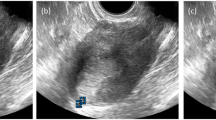

Drop metastases. (a) Small, dissociated fragments of serous carcinoma amidst atrophic endometrium; (b) A drop metastasis from a high-grade serous carcinoma of fallopian tube that involves secretory endometrium. (This figure was published in Uterine Pathology, Copyright Cambridge University Press, 2012).